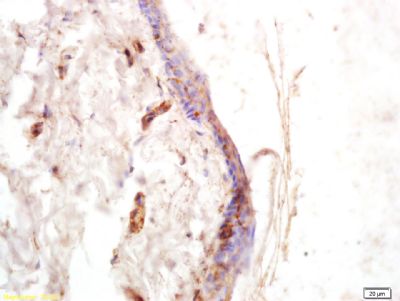

交叉反应Human,

COL6A5,6型胶原蛋白α5抗体产品应用WB=1:100-500 ELISA=1:500-1000 IHC-P=1:100-500 IHC-F=1:100-500 ICC=1:100-500 IF=1:100-500 (石蜡切片需做抗原修复)

Expressed in skin, followed by lung, small intestine, colon and testis. In skin, it is expressed in the epidermis with strongest staining in suprabasal viable layers. In ATOD patients, it is absent in the most differentiated upper spinous and granular layers (at protein level).